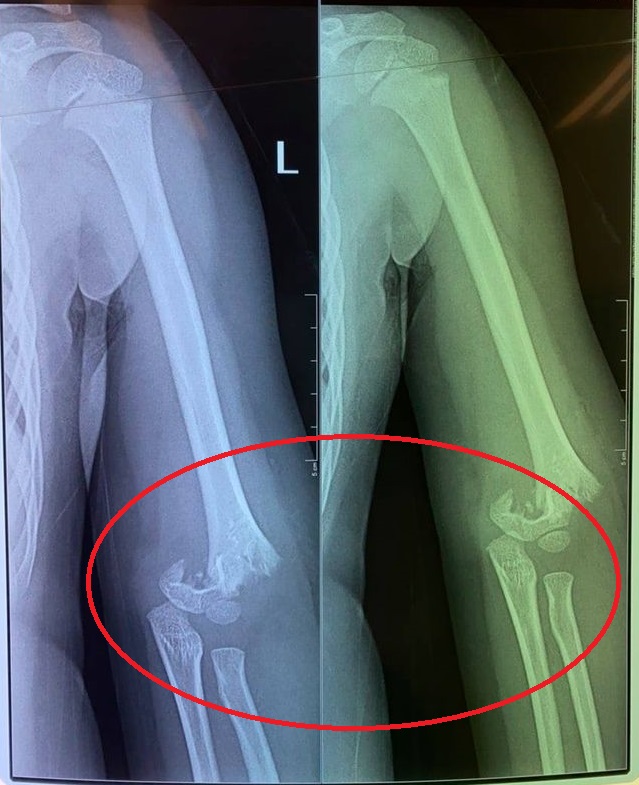

Con bị bạn đẩy ngã gẫy tay nhưng cô giáo không đưa đi cấp cứu ngay

Vụ việc này xảy ra vào ngày 15/9 ở trường mầm non Kid's Garden (Vườn trẻ thơ) tại tầng 1 nhà A3 chung cư số 250 Minh Khai, quận Hai Bà Trưng, Hà Nội. Chị N.T.T.H có con gái 5 tuổi tên B.T, hiện đang là học sinh của trường.

Chị H. cho biết: "Trong đợt dịch vừa qua, vì trường thiếu giáo viên nên lớp con chị chỉ có 1 cô chăm sóc 15 cháu. Điều này đã được phụ huynh phản ánh nhưng nhà trường vẫn chưa tuyển bổ sung giáo viên".

Sáng ngày 15/9, thời khóa biểu học có tiết chăm sóc cây xanh ở trường. Cô giáo đã cho học sinh ra khu vui chơi ngoài trời của chung cư (không phải của nhà trường), sau đó để các em chơi tự do.

Con chị H. đã bị 1 bạn cùng lớp đẩy ngã từ cầu trượt văng ra ngoài làm gãy khuỷu tay. Tuy nhiên nhà trường lại không đưa bé T. đi bệnh viện luôn. Con chị sau đó phải làm phẫu thuật ở bệnh viện Xanh Pôn.

"Điều quan trọng là con bị ngã gẫy tay từ sáng mà đến 12h trưa giáo viên mới cho con đi bệnh viện. Lúc con ngã, cô không đưa đi khám luôn mà lại đưa con vào lớp, để các bạn ăn uống xong xuôi rồi mới gọi một chiếc xe tư nhân đưa con đi mà không phải xe cấp cứu. Nếu là xe cấp cứu thì họ còn có thể sơ cứu, nẹp tay cho con", chị H. bức xúc cho biết.

Lãnh đạo Sở GD&ĐT Hà Nội cho biết, ngay sau khi tiếp nhận thông tin, đơn vị đã yêu cầu Phòng GD&ĐT quận Hai Bà Trưng xuống trường để nắm sự việc và cùng nhà trường giải quyết. Trước mắt, nhà trường và Phòng GD&ĐT tập trung thăm hỏi, lo cho sức khoẻ của trẻ.

Sau đó, Sở GD&ĐT yêu cầu, Phòng GD&ĐT, nhà trường phải xác minh, làm rõ sự việc xem trách nhiệm của giáo viên, nhà trường đến đâu. "Quan điểm của Sở GD&ĐT ngay từ đầu là ai sai đến đâu sẽ bị xử lý nghiêm đến đó", vị lãnh đạo này nói.